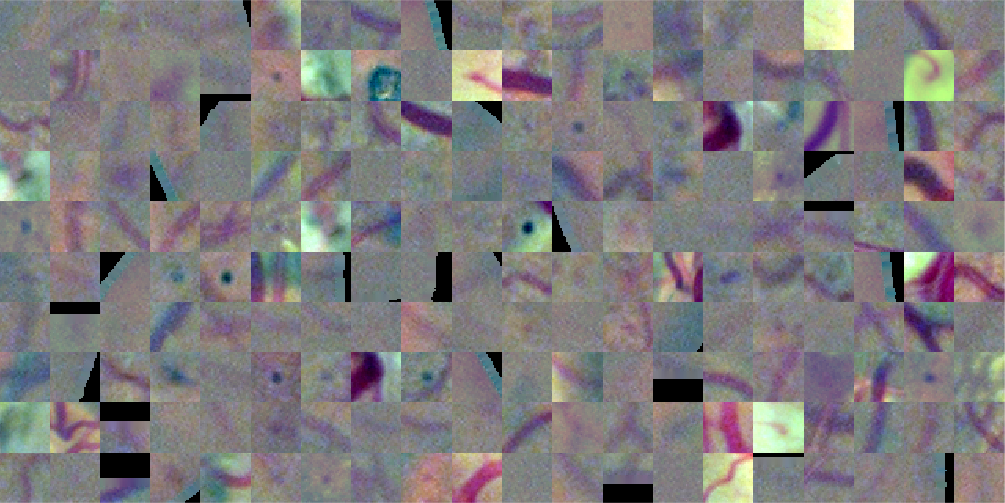

Figure 5 presents a random sample of the potential lesions retrieved by the method on a randomly selected image from DIARETDB1 training set. It is possible to see that most of false positive samples correspond to vascular branching or crossing points, vessel segments and beadings, scars due to laser photocoagulation or black spots of dirt in the capture device, as reported by Seoud et al. (2016). This setting underlines the importance of refine the candidates to remove false positives.

A training set is built for training the CNN, where each sample is a square patch around the center of each red lesion candidate, as extracted from (Figure 5). The patch size is taken as double the length of the major axis of the candidate, or pixels if the major axis of the candidate is smaller than 32 pixels. This setting let us to recover not only the candidate itself but also its surrounding area, which allows the CNN to capture both candidates’ internal features and information about its shape, borders and context. Patches larger than pixels are downsized to this resolution to ensure a uniform input size for the CNN. As windows are square by definition, this transformation is isotropic and does not affect the appearance of the lesion candidate. Samples are centered by subtracting the training set mean image. Alternative scaling methods such as ZCA whitening and contrast normalization were also analyzed, although no improvements were observed on the validation set when applying them. The label associated to the candidate is assigned according to the ground truth labeling on the data set: if the candidate overlaps with a true labeled region, then the window is assumed to be a true red lesion (); if it does not, then it is assumed to be a false positive (). The CNN is trained from scratch on an augmented version of this training set, which is obtained by rotating each patch by or , and then flipping the resulting windows horizontally or not. Thus, for each input patch, 8 new patches are generated.

In order to assess the visual appearance of the deep learned features, a graphical representation of the 32 filters of size learned on the first layer of the CNN is presented in Figure 13. These representations allow to verify which types of high level characteristics are detected by the first layer of the network (Zeiler and Fergus, 2014). Thus, they are suitable to confirm if the network was trained for long enough, as well-trained CNNs usually display smooth filters without noisy patterns, as in this case. From Figure 13(a) it is possible to see that filters learned in Experiment 1 are mostly descriptors of the color properties of the lesions. This setting is in line with the fact that the training set used in this case contains not only small MAs but also medium size HEs, which can be more easily described in terms of their internal color homogeneity rather than their edges, which significantly varies from one to another. Other filters are able to capture purple, ellipsoidal structures corresponding to true lesions like those illustrated in Figure 5(b). This last type of filter is more common in the first layer of the CNN learned in Experiment 2 (Figure 13(b), which might be associated with the smaller true positive structures observed in the training set built with ROC and DIARETDB1 MAs.